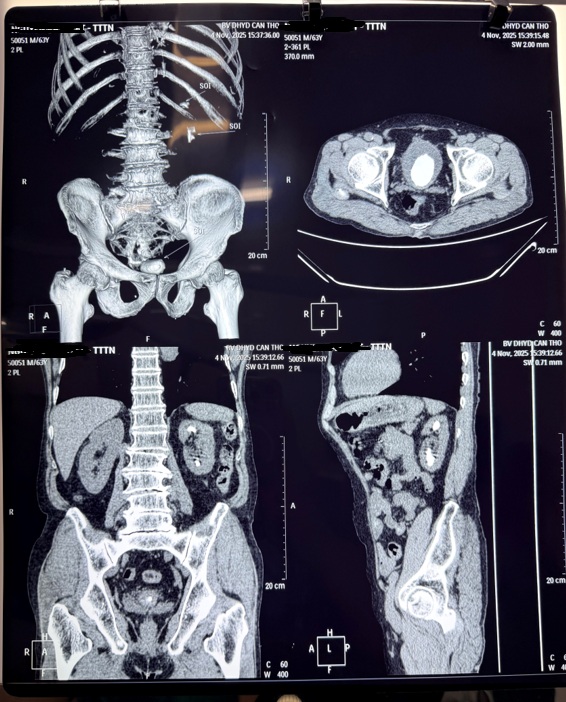

Vừa qua, Bệnh viện Trường Đại học Y Dược Cần Thơ đã tiếp nhận một trường hợp bệnh nhân nam 63 tuổi nhập viện với triệu chứng đau hạ vị, tiểu rất khó, tiểu buốt kéo dài, tiểu ngắt quãng và tiểu máu. Sau khi chụp cắt lớp vi tính ghi nhận bệnh nhân có một viên sỏi kích thước lớn với kt 46x35x31mm, chiếm gần toàn bộ lòng bàng quang, gây bế tắc dòng tiểu, nguy cơ bí tiểu và nhiễm trùng.

Hình 1. CT-scan trước phẫu thuật cho thấy sỏi lớn